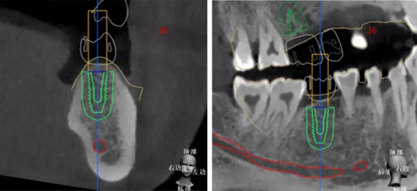

繪制下頜神經(jīng)管

種植規(guī)劃與術(shù)后CBCT影像對(duì)比